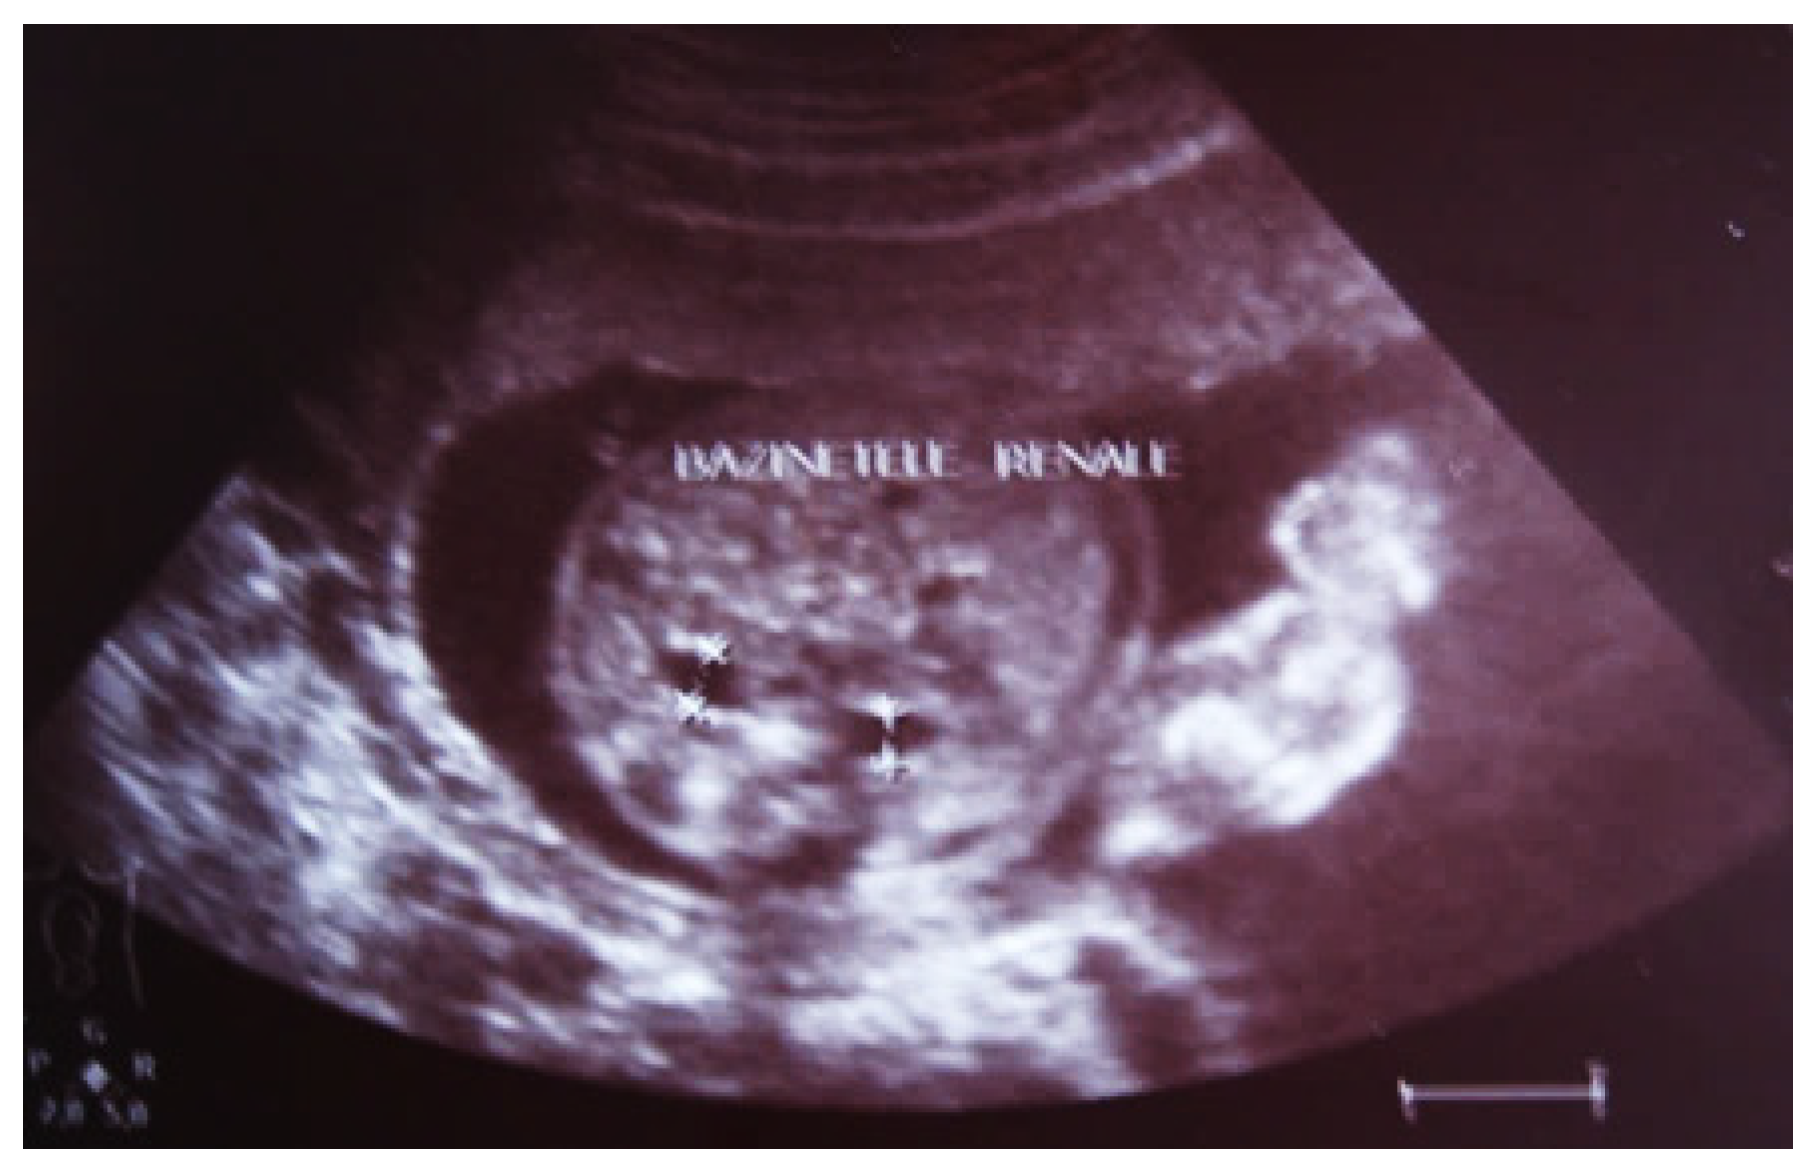

Our experience with congenital malformations of the urinary system refers to the following clinical case (Figure 2, Figure 3, Figure 4, Figure 5, Figure 6, Figure 7, Figure 8 and Figure 9). In the first case, during pregnancy, the 21-week ultrasound determined bilateral renal pyelectasia. The fetus had hydronephrosis on the right; at 31 weeks, it had bilateral hydrocalconephrosis; and at 32 weeks, bilateral pyelectasia. It suffered premature birth at 36 weeks, with complicated anomalies of the forces of contraction, prolonged birth, and birth weight of 2200 g. Postnatal ultrasonography was supplemented by intravenous urography, and bilateral hydronephrosis was determined. Hydrocalconephrosis on the left was discovered. The complete diagnosis was established: congenital renal malformation; bilateral pyelectasia; bilateral hydronephrosis; hydrocalconephrosis on the left; and severe reduced glomerular filtration rate (GFR), GFR > 2SD below mean.

Figure 6. Ultrasound of the postnatal urinary system 10 days after birth. Hydronephrosis on the right.

Figure 7. Postnatal urinary ultrasound. Hydronephrosis on the right (newborn 10 days of age).

Figure 8. Postnatal urinary ultrasound. Hydronephrosis on the left.